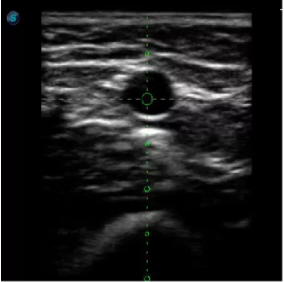

實時觀察穿刺針進入血管的全過程,方便操作及較短的穿刺路徑,智能進針尺寸提示,讓置管工作更加輕松,高效。

不同進針路徑